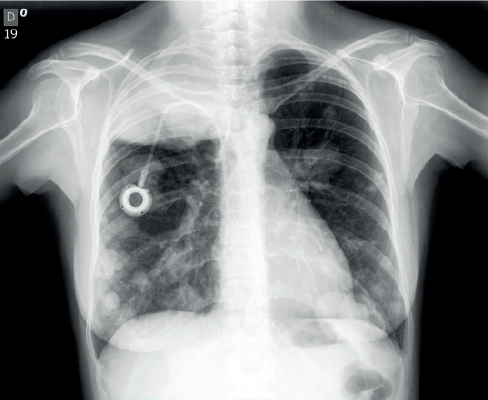

Já o tumor trofoblástico epiteloide cursa com sangramento transvaginal irregular, comumente após a gestação. Apresentam baixos níveis de β-hCG, e metástases pulmonares acometem até 25% das pacientes.

Assim, sintomas respiratórios, como tosse, dor torácica e hemoptise, bem como hemorragias cerebrais, gastrointestinais e urológicas são indicativos de doença metastática. Para mais, em casos de acometimento hepático, a paciente pode referir dor epigástrica ou em quadrante superior direito.

Após diagnóstico são necessárias a realização de novos exames clínicos e ginecológicos, através da inspeção de órgãos genitais externos e do exame especular, bem como USG transvaginal com dopplerfluxometria e uma radiografia de tórax, uma vez que os pulmões são os órgãos mais comumente acometidos por metástase.